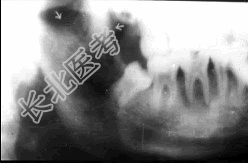

单项选择题可出现大块分界不清的死骨为 ( )

A、急性中央性骨髓炎

B、慢性化脓性骨髓炎

C、边缘性骨髓炎

D、放射性骨髓炎

E、婴幼儿骨髓炎